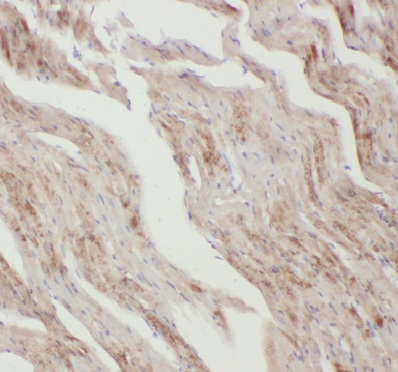

| 验证图片 | Immunohistochemistry of paraffin-embedded mouse heart tissue using FNab00478(anti- Apelin antibody) at dilution of 1:200 |